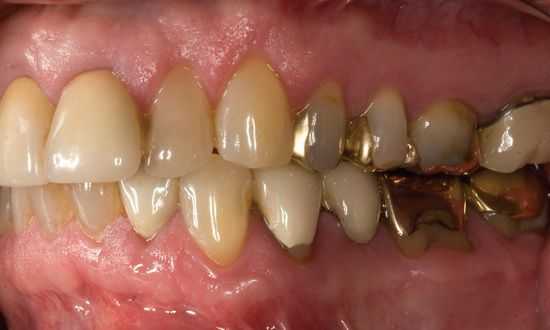

- На передних зубах нижней челюсти в области шейки имеются отложения твёрдой консистенции (зубной камень).

- Межзубные сосочки гиперемированы (есть покраснение) и кровоточат при пальпации (нажатии).

- На верхней челюсти стоит бюгельный протез, в области жевательных зубов нижней челюсти слева — мостовидный протез с опорами на 36 и 33 зубы с покрытием из нитрид титана (под золото).

- Слизистая полости рта вестибулярной поверхности бледно-розового цвета, слизистая нёба, язычной поверхности и языка гиперемирована.